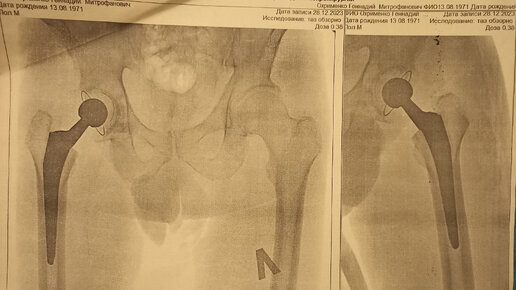

3 дня после замены ТБС и Вы здоровы.

Замена тазобедренного сустава